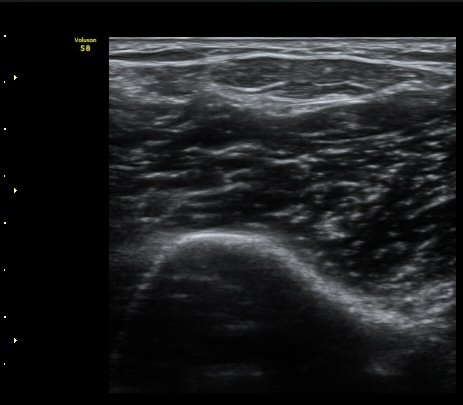

ÃÊÀ½ÆÄ °Ë»ç

ÆÈ²ÞÄ¡ ¾Õ Ⱦ´Ü¸é°Ë»ç¿¡¼­ À̵ιڱÙÀÌ ÈûÁÙ·Î ÀÌÇàµÇ´Â °ÍÀÌ °üÂûµÈ´Ù(±×¸² 1, 2).

ŽÃËÀÚ¸¦ Á¶±Ý ¸»´ÜÀ¸·Î À̵¿ÇÏ´Ï À̵ιڱ٠ÈûÁÙÀÌ ¶Ñ·ÈÇÏ°Ô °üÂûµÇ°í ÇÔÁÙ ÁÖÀ§¿¡

¼ö¾×Àú·ù°¡  º¸ÀδÙ(±×¸² 3, 4, 5, 6)